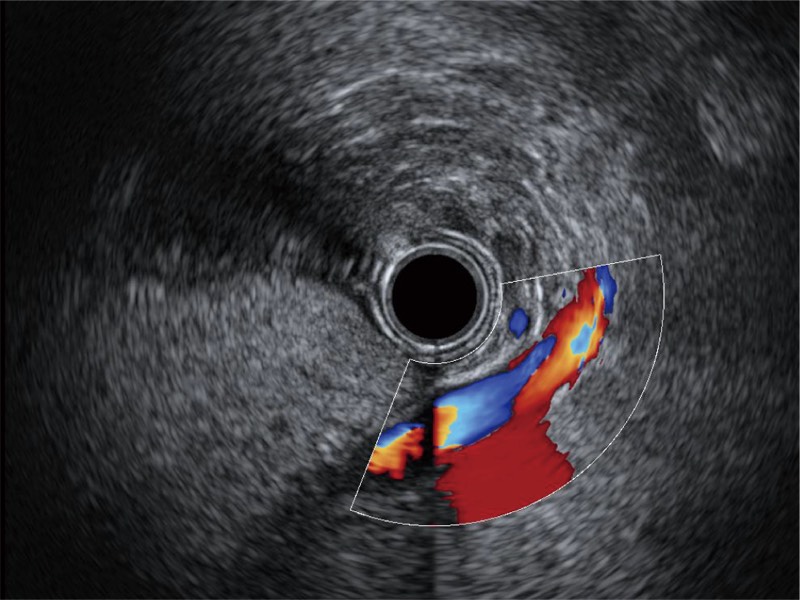

• 清晰显示胆总管及周围血管分布

• 伪彩(Chroma)

可人为将灰阶图像转变成彩色的显示方式,增强人眼对于不同回声强度的敏感度,主观上增加了图像分辨率